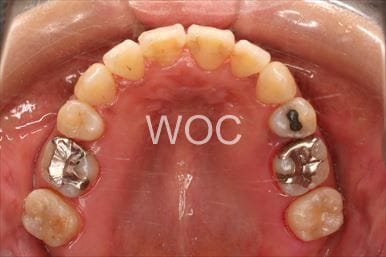

八重歯・叢生上のみ舌側矯正、下はエッジワイズ装置

上は舌側矯正を希望。ガタガタ(叢生)が強い。上顎右側中切歯・側切歯が歯科治療で連結してあったがそれを除去してから治療開始しました。

- 年齢:23歳女性

- 主訴:上下前歯のガタガタが気になる

- 基本矯正料金:103万円

- 治療期間:2年2ヶ月

- 非抜歯